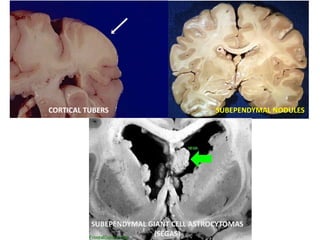

CORTICAL TUBERS SUBEPENDYMAL NODULES

SUBEPENDYMAL GIANT CELL ASTROCYTOMAS

(SEGAS)

CORTICAL TUBERS

• other intracranial abnormalities, such as

cortical dysplasia and white matter linear

SUBEPENDYMAL NODULES

• Small, usually asymptomatic calcifications projecting

from the ependymal surface of the lateral ventricles.

• Pathologically similar to SEGAs but do not show

SEGAs

• Manifest during the first two decades

• Benign tumors of neuroglial origin (5% to

20% of TSC)

• Slow-growing tumors, typically found at

the caudothalamic groove adjacent to

the foramen of Monro

CORTICAL TUBERS SUBEPENDYMALNODULES SUBEPENDYMAL GIANT CELL ASTROCYTOMAS (SEGAS)

• Smooth, firm,pale gliotic plaques typically distributed along GW matter jn • Hamartomas of abnormal neurons and glia • Can act as seizure foci CORTICAL TUBERS

• other intracranialabnormalities, such as cortical dysplasia and white matter linear migration lines, are visible on imaging.

SUBEPENDYMAL NODULES • Small,usually asymptomatic calcifications projecting from the ependymal surface of the lateral ventricles. • Pathologically similar to SEGAs but do not show enhancement with contrast material

SEGAs • Manifest duringthe first two decades • Benign tumors of neuroglial origin (5% to 20% of TSC) • Slow-growing tumors, typically found at the caudothalamic groove adjacent to the foramen of Monro